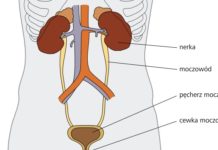

Czy można uchronić się samemu przed zakażeniem układu moczowego?

Samodzielnie lub z pomocą odpowiedniego specjalisty zadbaj o swoje drogi moczowe

W przypadku dostania się i zamieszkania bakterii w układzie moczowym mamy do czynienia z...